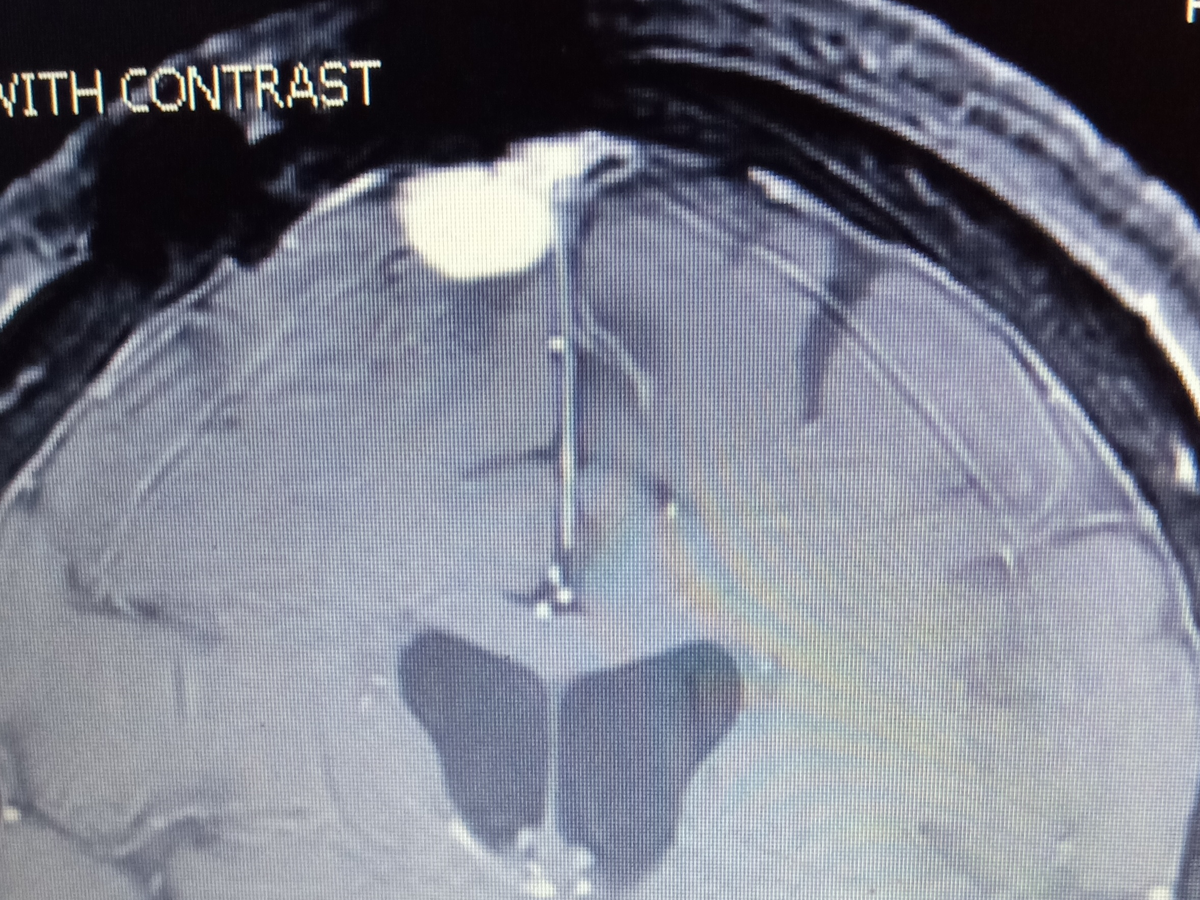

Unfortunately, my brain tumor is growing and with a second craniotomy, location of the tumor, I am likely to encounter more difficulties (possible stroke, more vision loss, more seizures, and more intense falls). I will also need radiation to the remaining tumor to hopefully stunt the possibility of regrowth.